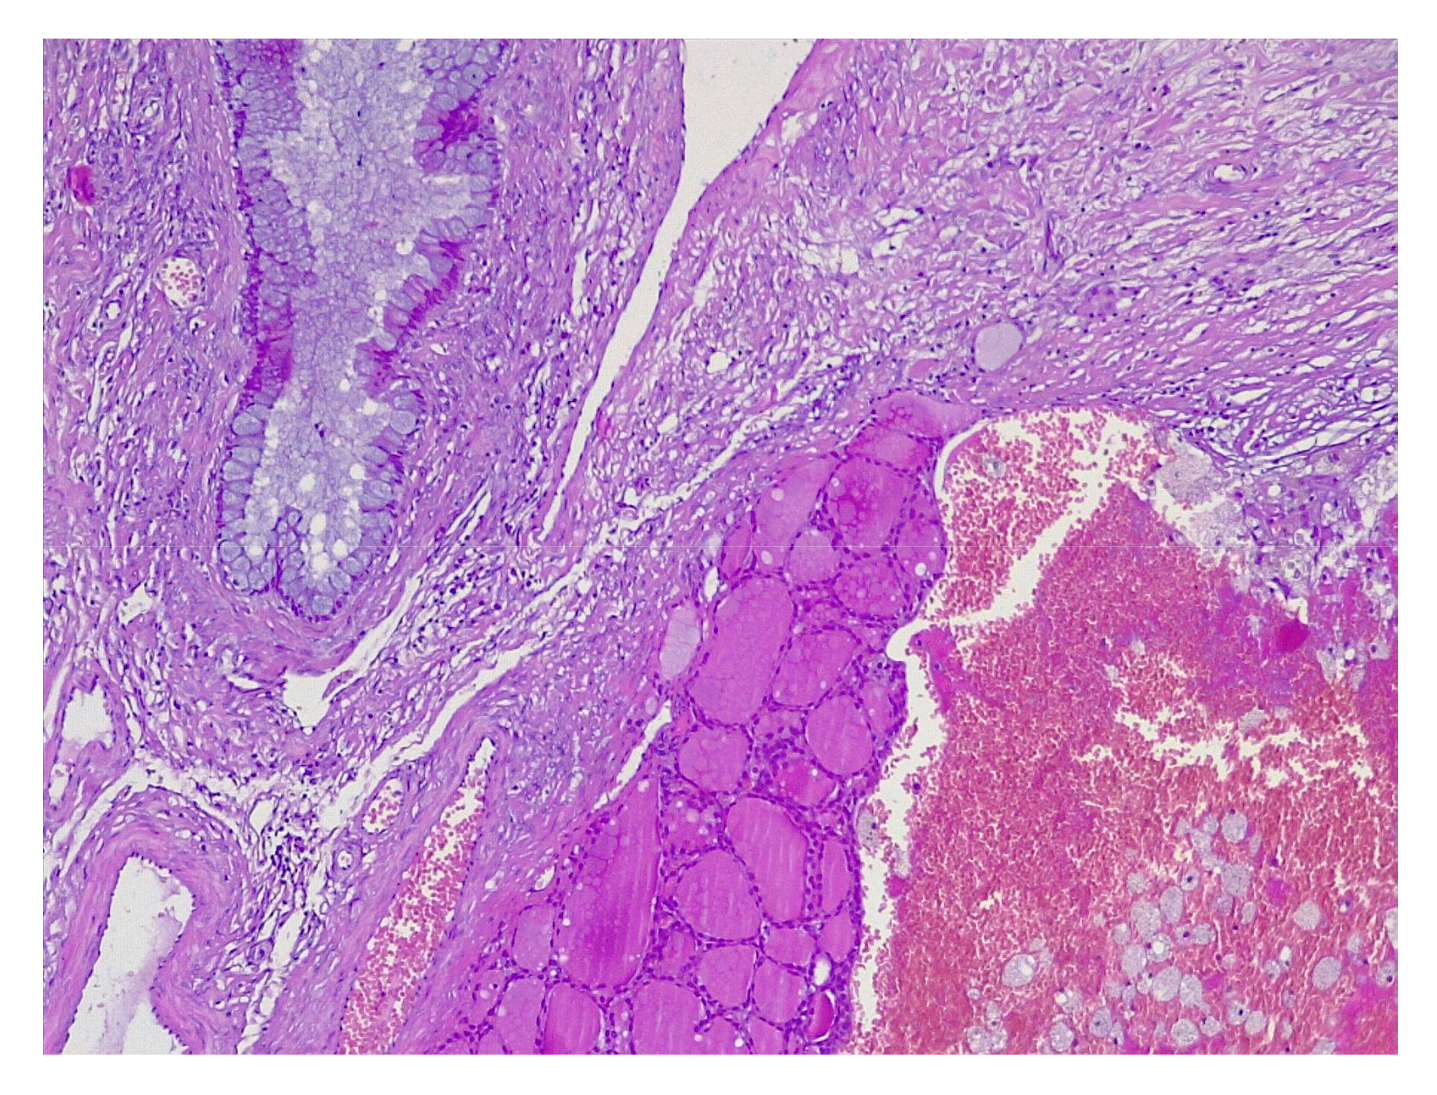

4.2. Histopathology Features